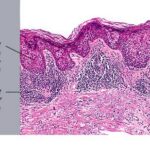

Bowen disease

Bowen disease is a full-thickness anaplasia of the epidermis, with loss of the normal maturation of its components. Keratinocytes are atypical and disorderly, often described as having a windblown appearance. Although the basal cell layer is intact, extension of keratinocyte atypia down the follicular epithelium is seen. Vacuolization, mitoses, individually keratinizing cells, and multinucleated cells are present in the epidermis. Large pale keratinocytes with abundant ground-glass cytoplasm, so-called pagetoid cells, often are distributed haphazardly throughout the epidermis. Hyperkeratosis, parakeratosis, and acanthosis are seen to some degree in lesions of Bowen disease. The upper dermis has a moderate lymphocytic infiltrate.